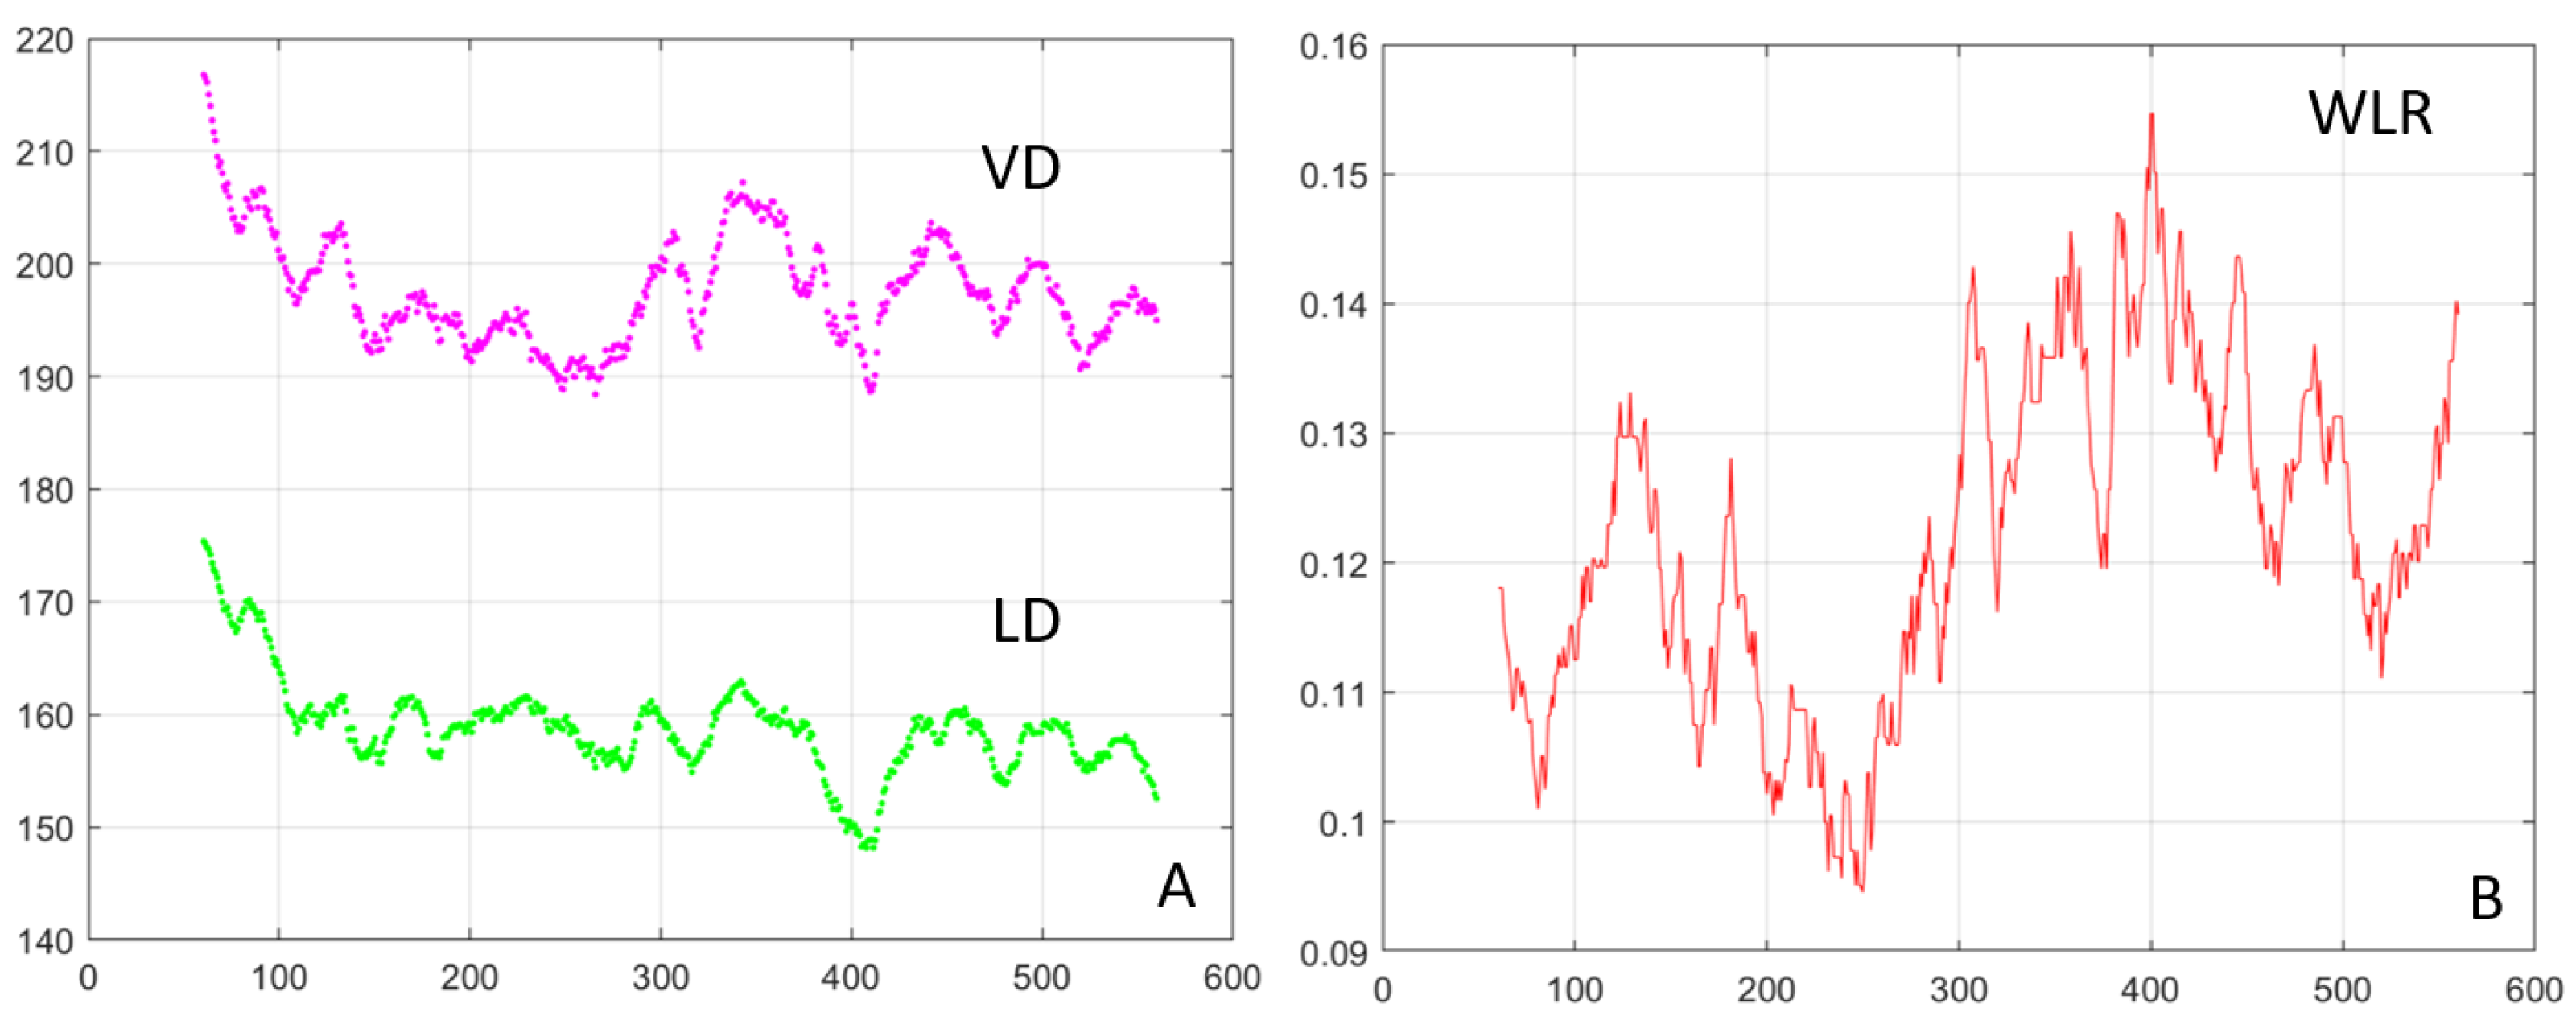

3. Results

4. Discussion